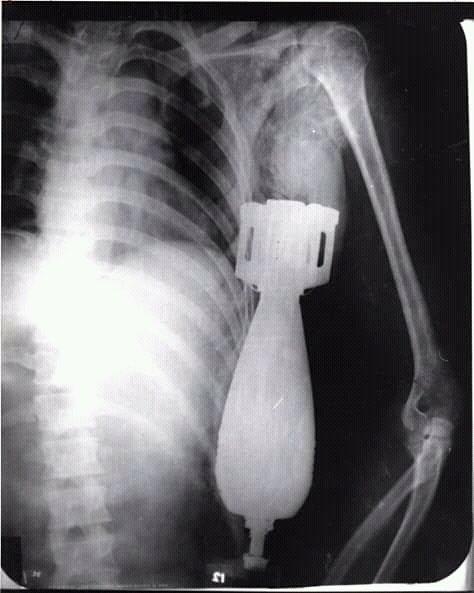

越南共和国陆军士兵阮文龙(Nguyen Van Luong)乘坐着步战车,到达了指定地点,当他刚打开门下车时,越南南方民族解放阵线就用迫击炮轰击南越部队的集结点,一枚60毫米迫击炮炮弹从天而降,砸到了阮文龙的M1头盔上,随后阮文龙因头部受到剧烈冲击而陷入了昏迷。阮文龙是幸运的,只因为巧合,这枚炮弹在他的头盔上发生了跳弹而且这枚炮弹也并未发生爆炸;同时阮文龙也是不幸的,被弹开的炮弹顺势从他的锁骨处钻入了他的胸腔,弹头部分又从他左侧肋骨下方钻出头来。

阮文龙的X光照

之后,阮文龙的战友小心翼翼地将他送到了岘港海军医院,美军军医哈利·丁斯摩尔(Dr.Harry Dinsmore)为其进行外科手术。因为这枚炮弹仍有爆炸的可能,因此哈利·丁斯摩尔疏散了医院的人群,并让其他士兵在手术室外用沙袋构筑了防爆工事。当一切处理妥当后,哈利·丁斯摩尔为阮文龙拍摄了X光图片,最终确定这枚炮弹没有卡在骨头上,也没有伤及阮文龙的脏器,随后哈利·丁斯摩尔决定立即对阮文龙展开外科手术。